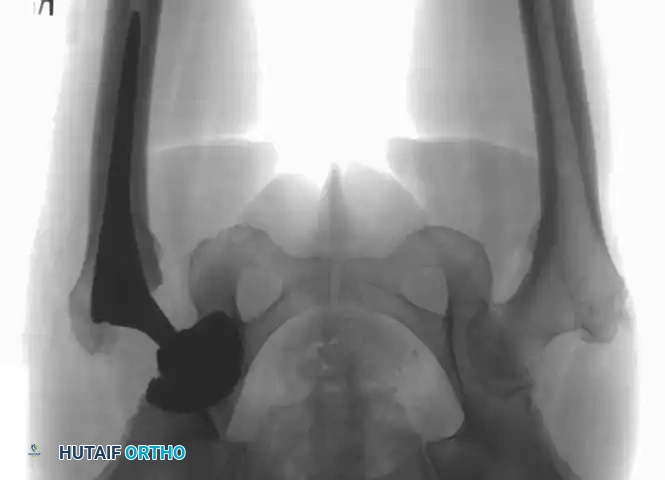

Management of Irreducible Dislocations

While most acetabular fractures are not surgical emergencies, an irreducible fracture-dislocation of the hip is a notable exception. The historical term "central fracture-dislocation" describes a severe medial subluxation of the femoral head into the true pelvis.

Fig. 53-3 Transverse acetabular fracture with true central fracture-dislocation; intrapelvic femoral head can become locked between superior and inferior fracture fragments.

In these scenarios, the femoral head may become incarcerated between the superior and inferior fracture fragments, rendering closed reduction impossible.

Associated Surgical & Radiographic Imaging

Hutaifortho's Orthopaedic Diagram